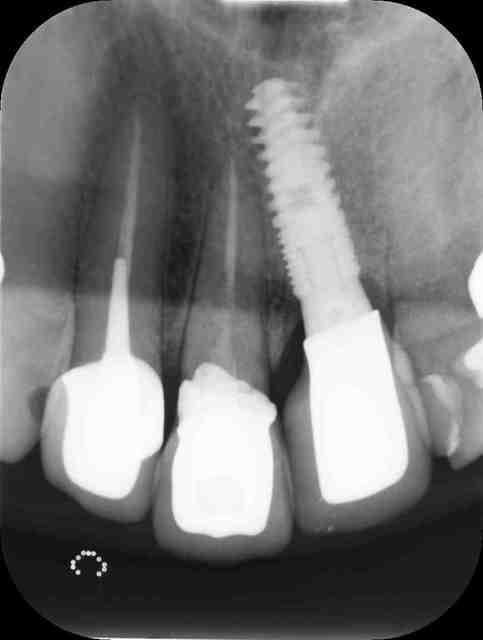

Ci-joint la photo des contacts photographiés lors de la précédente visite (13/05, après retouches occlusales), et la radio de ce jour.

Pour info restauration sur implant 21 : 16/06/2010